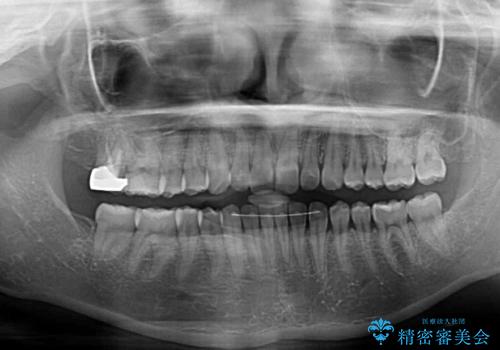

根管治療された歯に症状はなく、オールセラミッククラウンにて補綴治療を行うこととしました。

クラウンはよりよい咬み合わせで装着したいため、インビザラインを1セット使用して概ね歯列を整えた時点で補綴治療を行い、その後仕上げの矯正治療を行いました。